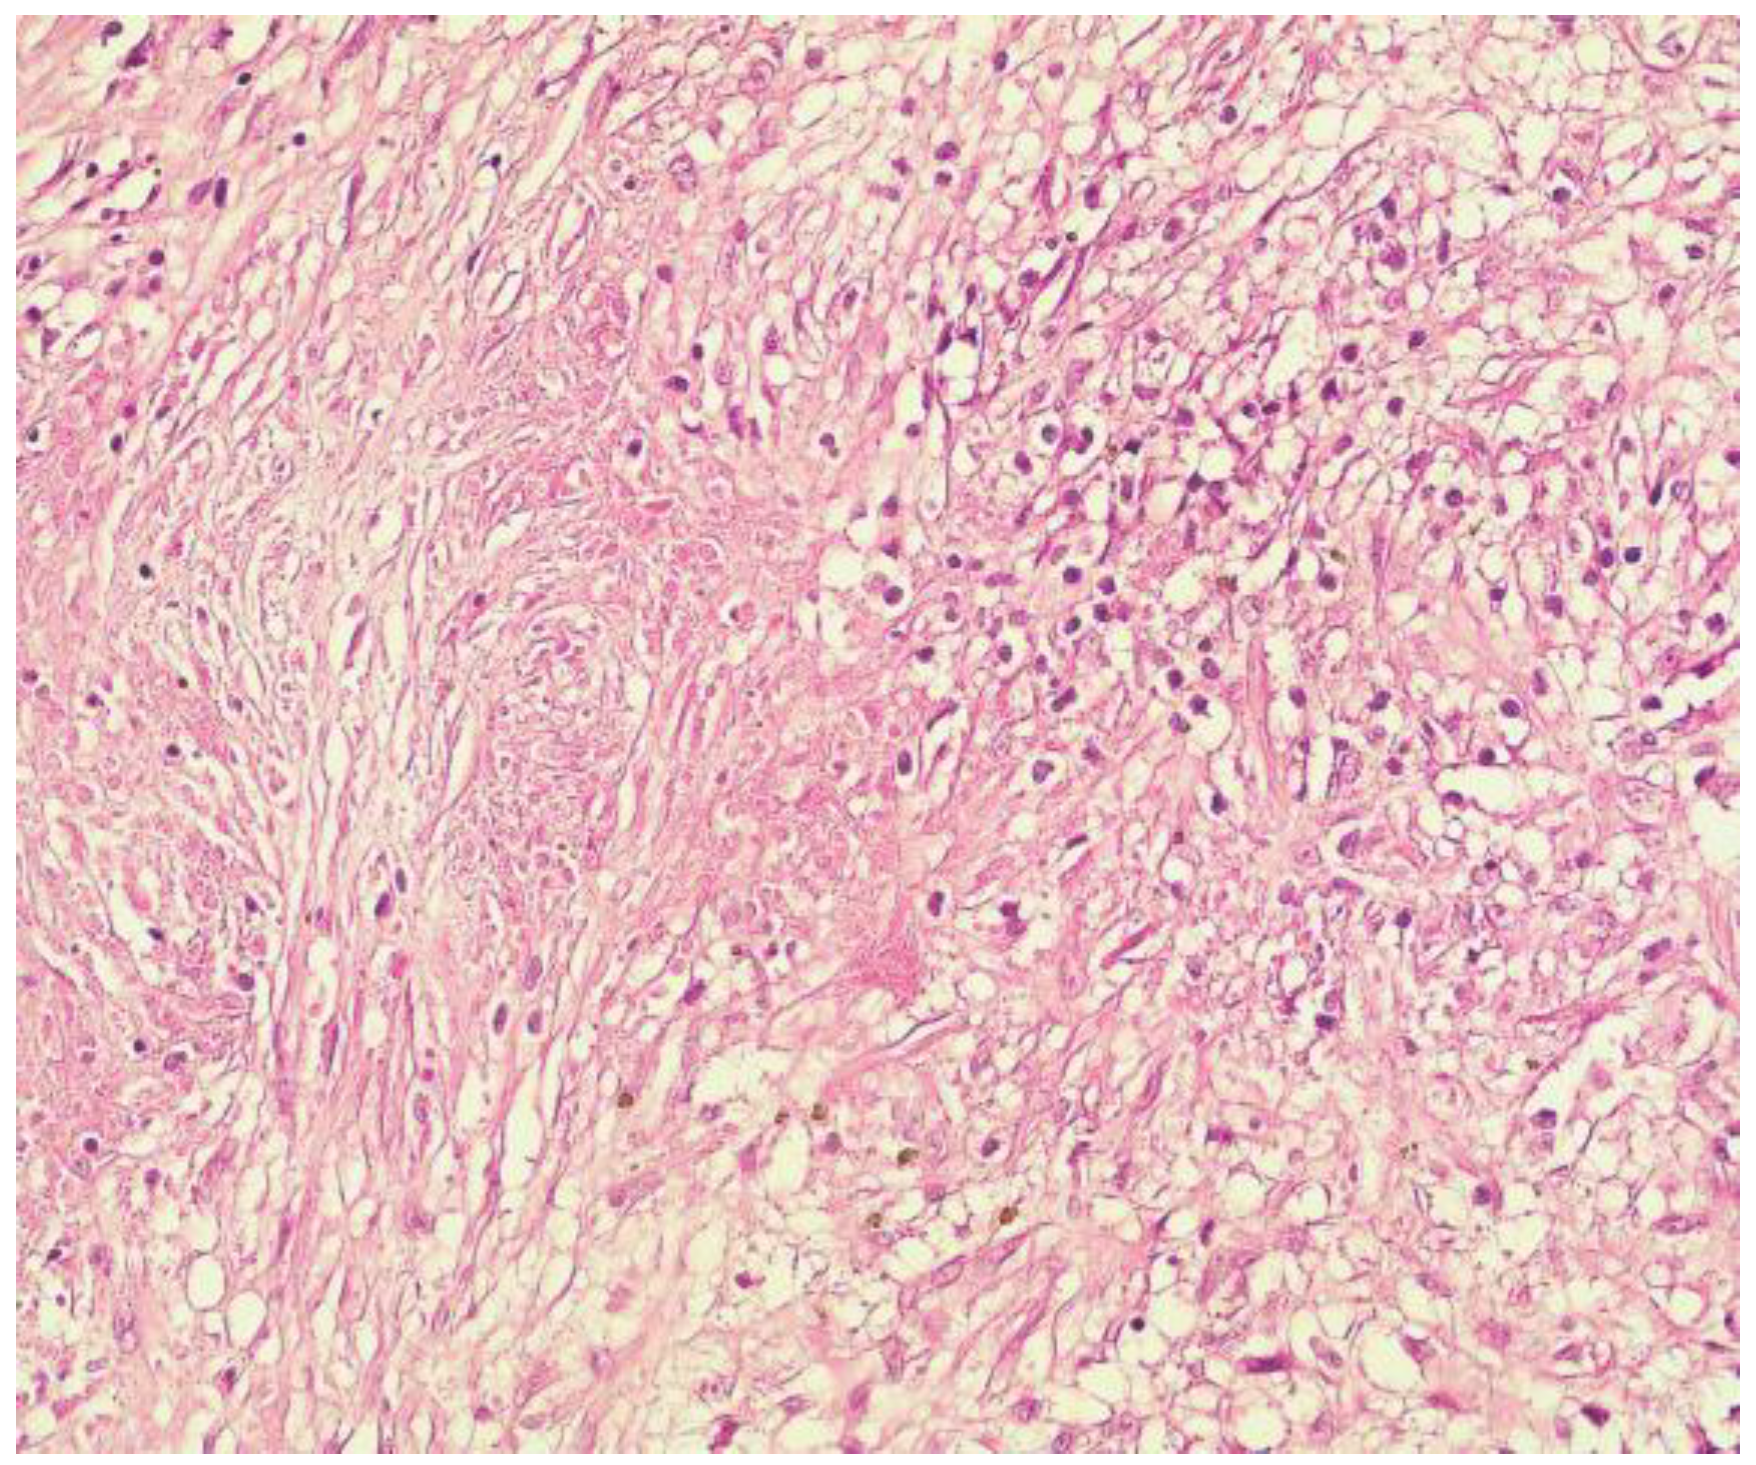

4. Diagnosis